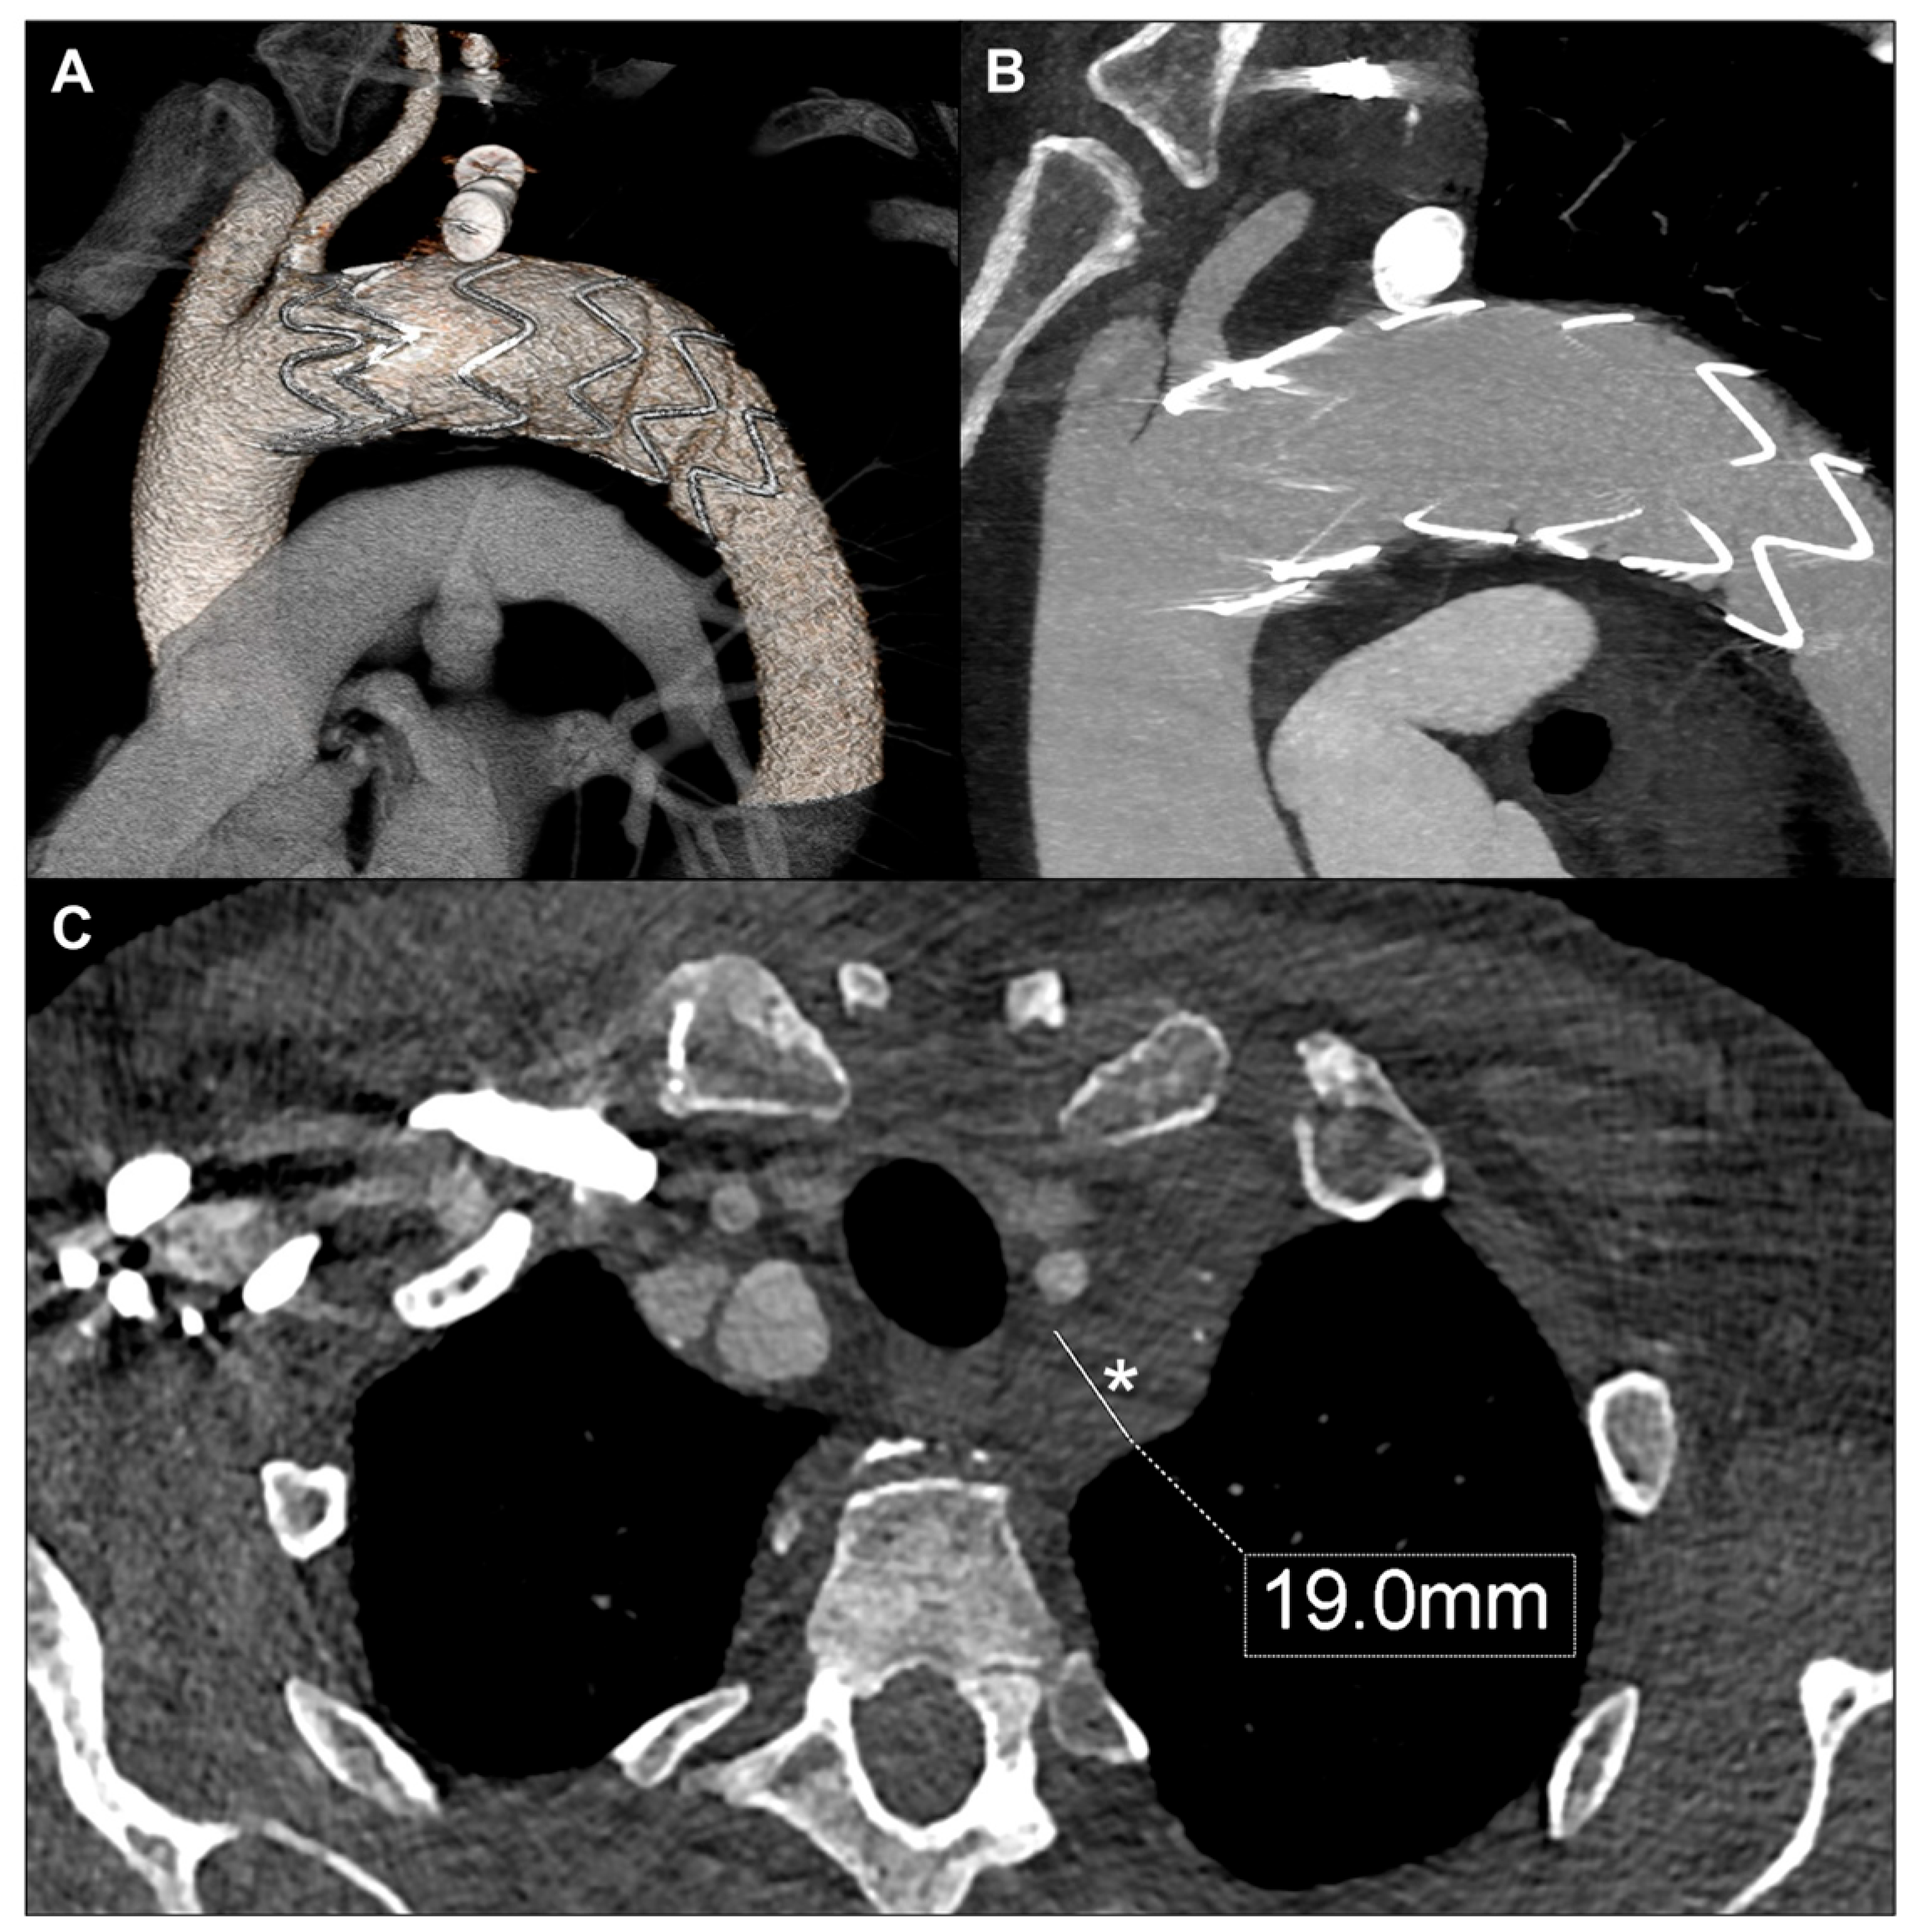

2. Case Report